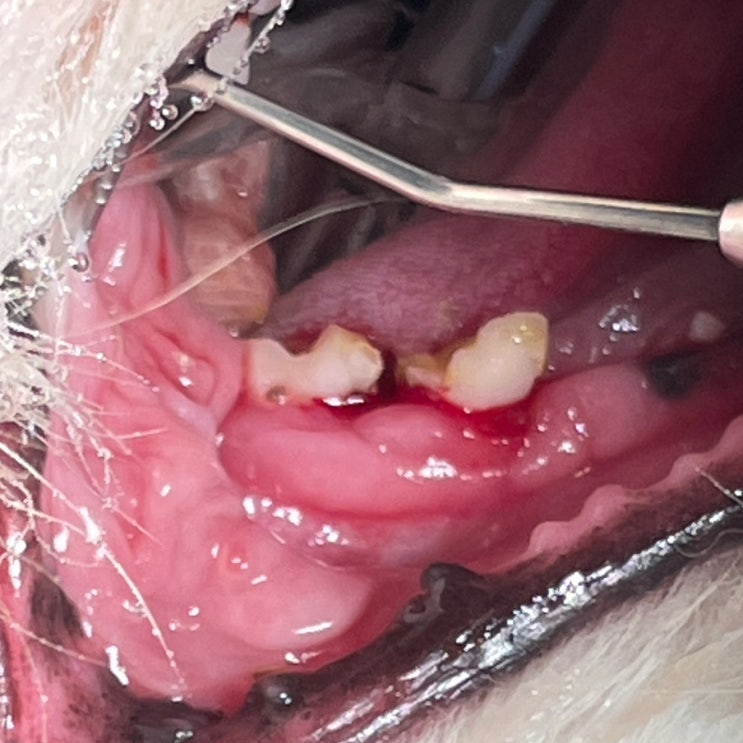

심장병 있는 8살 포메라니안 강아지 스케일링, 발치 후기 / 심장병 있는 반려견 마취하면 안 되나요? / 댕댕이 치아 부러지면 어떻게 해야 하나요? / 강아지 발치 잘하는 수의사

안녕하세요~ 굿파파 수의사입니다. 어제부터 봄비가 계속 내리네요~^^* 산과 들이 초록으로 물들어가네요~ ...